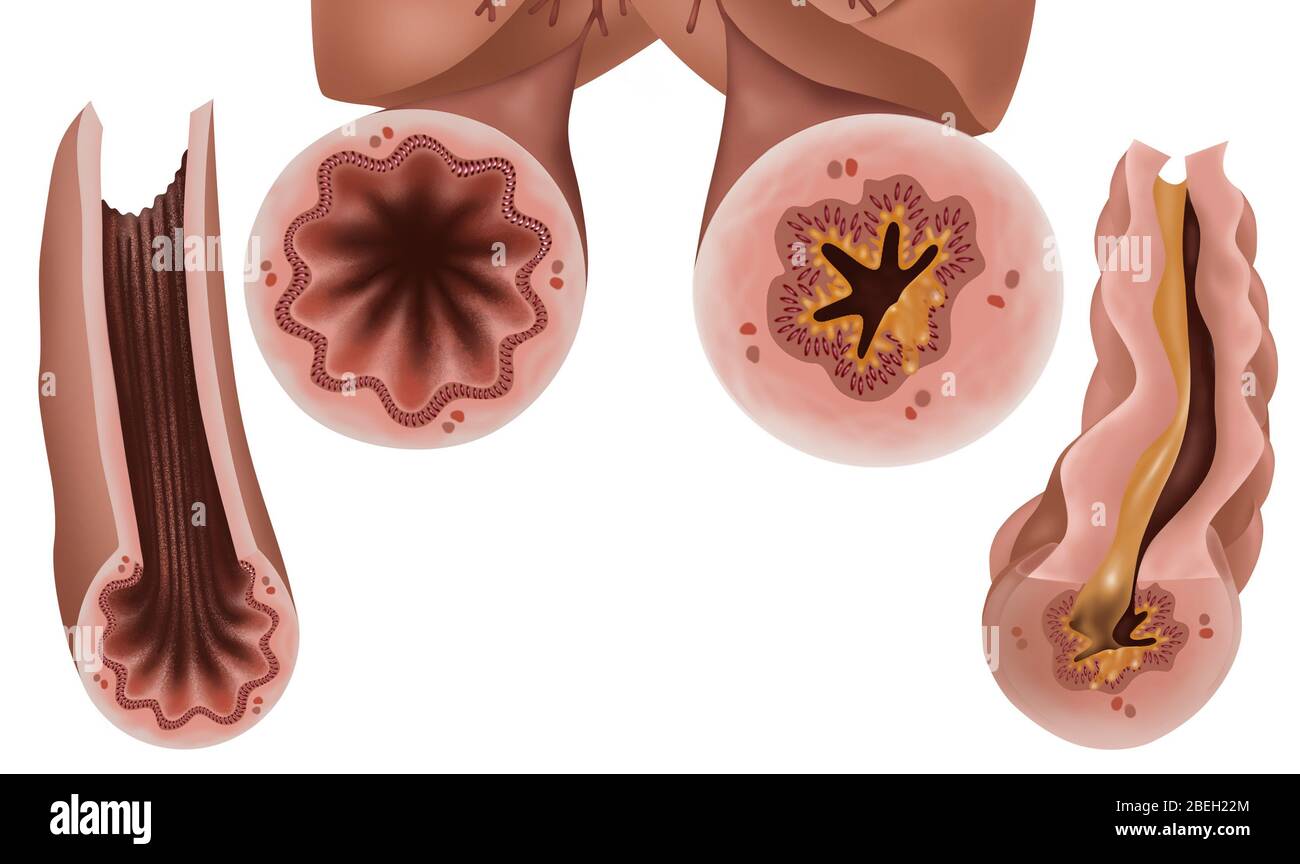

Lungs - Bronchial Mucus. Shown is bronchial airway obstruction and narrowing due to viscid mucus. Stock Photohttps://www.alamy.com/image-license-details/?v=1https://www.alamy.com/stock-photo-lungs-bronchial-mucus-shown-is-bronchial-airway-obstruction-and-narrowing-130806404.html

Lungs - Bronchial Mucus. Shown is bronchial airway obstruction and narrowing due to viscid mucus. Stock Photohttps://www.alamy.com/image-license-details/?v=1https://www.alamy.com/stock-photo-lungs-bronchial-mucus-shown-is-bronchial-airway-obstruction-and-narrowing-130806404.htmlRFHGPMW8–Lungs - Bronchial Mucus. Shown is bronchial airway obstruction and narrowing due to viscid mucus.

Shown is bronchial airway obstruction and narrowing due to viscid mucus. Excessive mucus in bronchial airways can cause significant obstruction and an Stock Photohttps://www.alamy.com/image-license-details/?v=1https://www.alamy.com/stock-photo-shown-is-bronchial-airway-obstruction-and-narrowing-due-to-viscid-130806403.html

Shown is bronchial airway obstruction and narrowing due to viscid mucus. Excessive mucus in bronchial airways can cause significant obstruction and an Stock Photohttps://www.alamy.com/image-license-details/?v=1https://www.alamy.com/stock-photo-shown-is-bronchial-airway-obstruction-and-narrowing-due-to-viscid-130806403.htmlRFHGPMW7–Shown is bronchial airway obstruction and narrowing due to viscid mucus. Excessive mucus in bronchial airways can cause significant obstruction and an